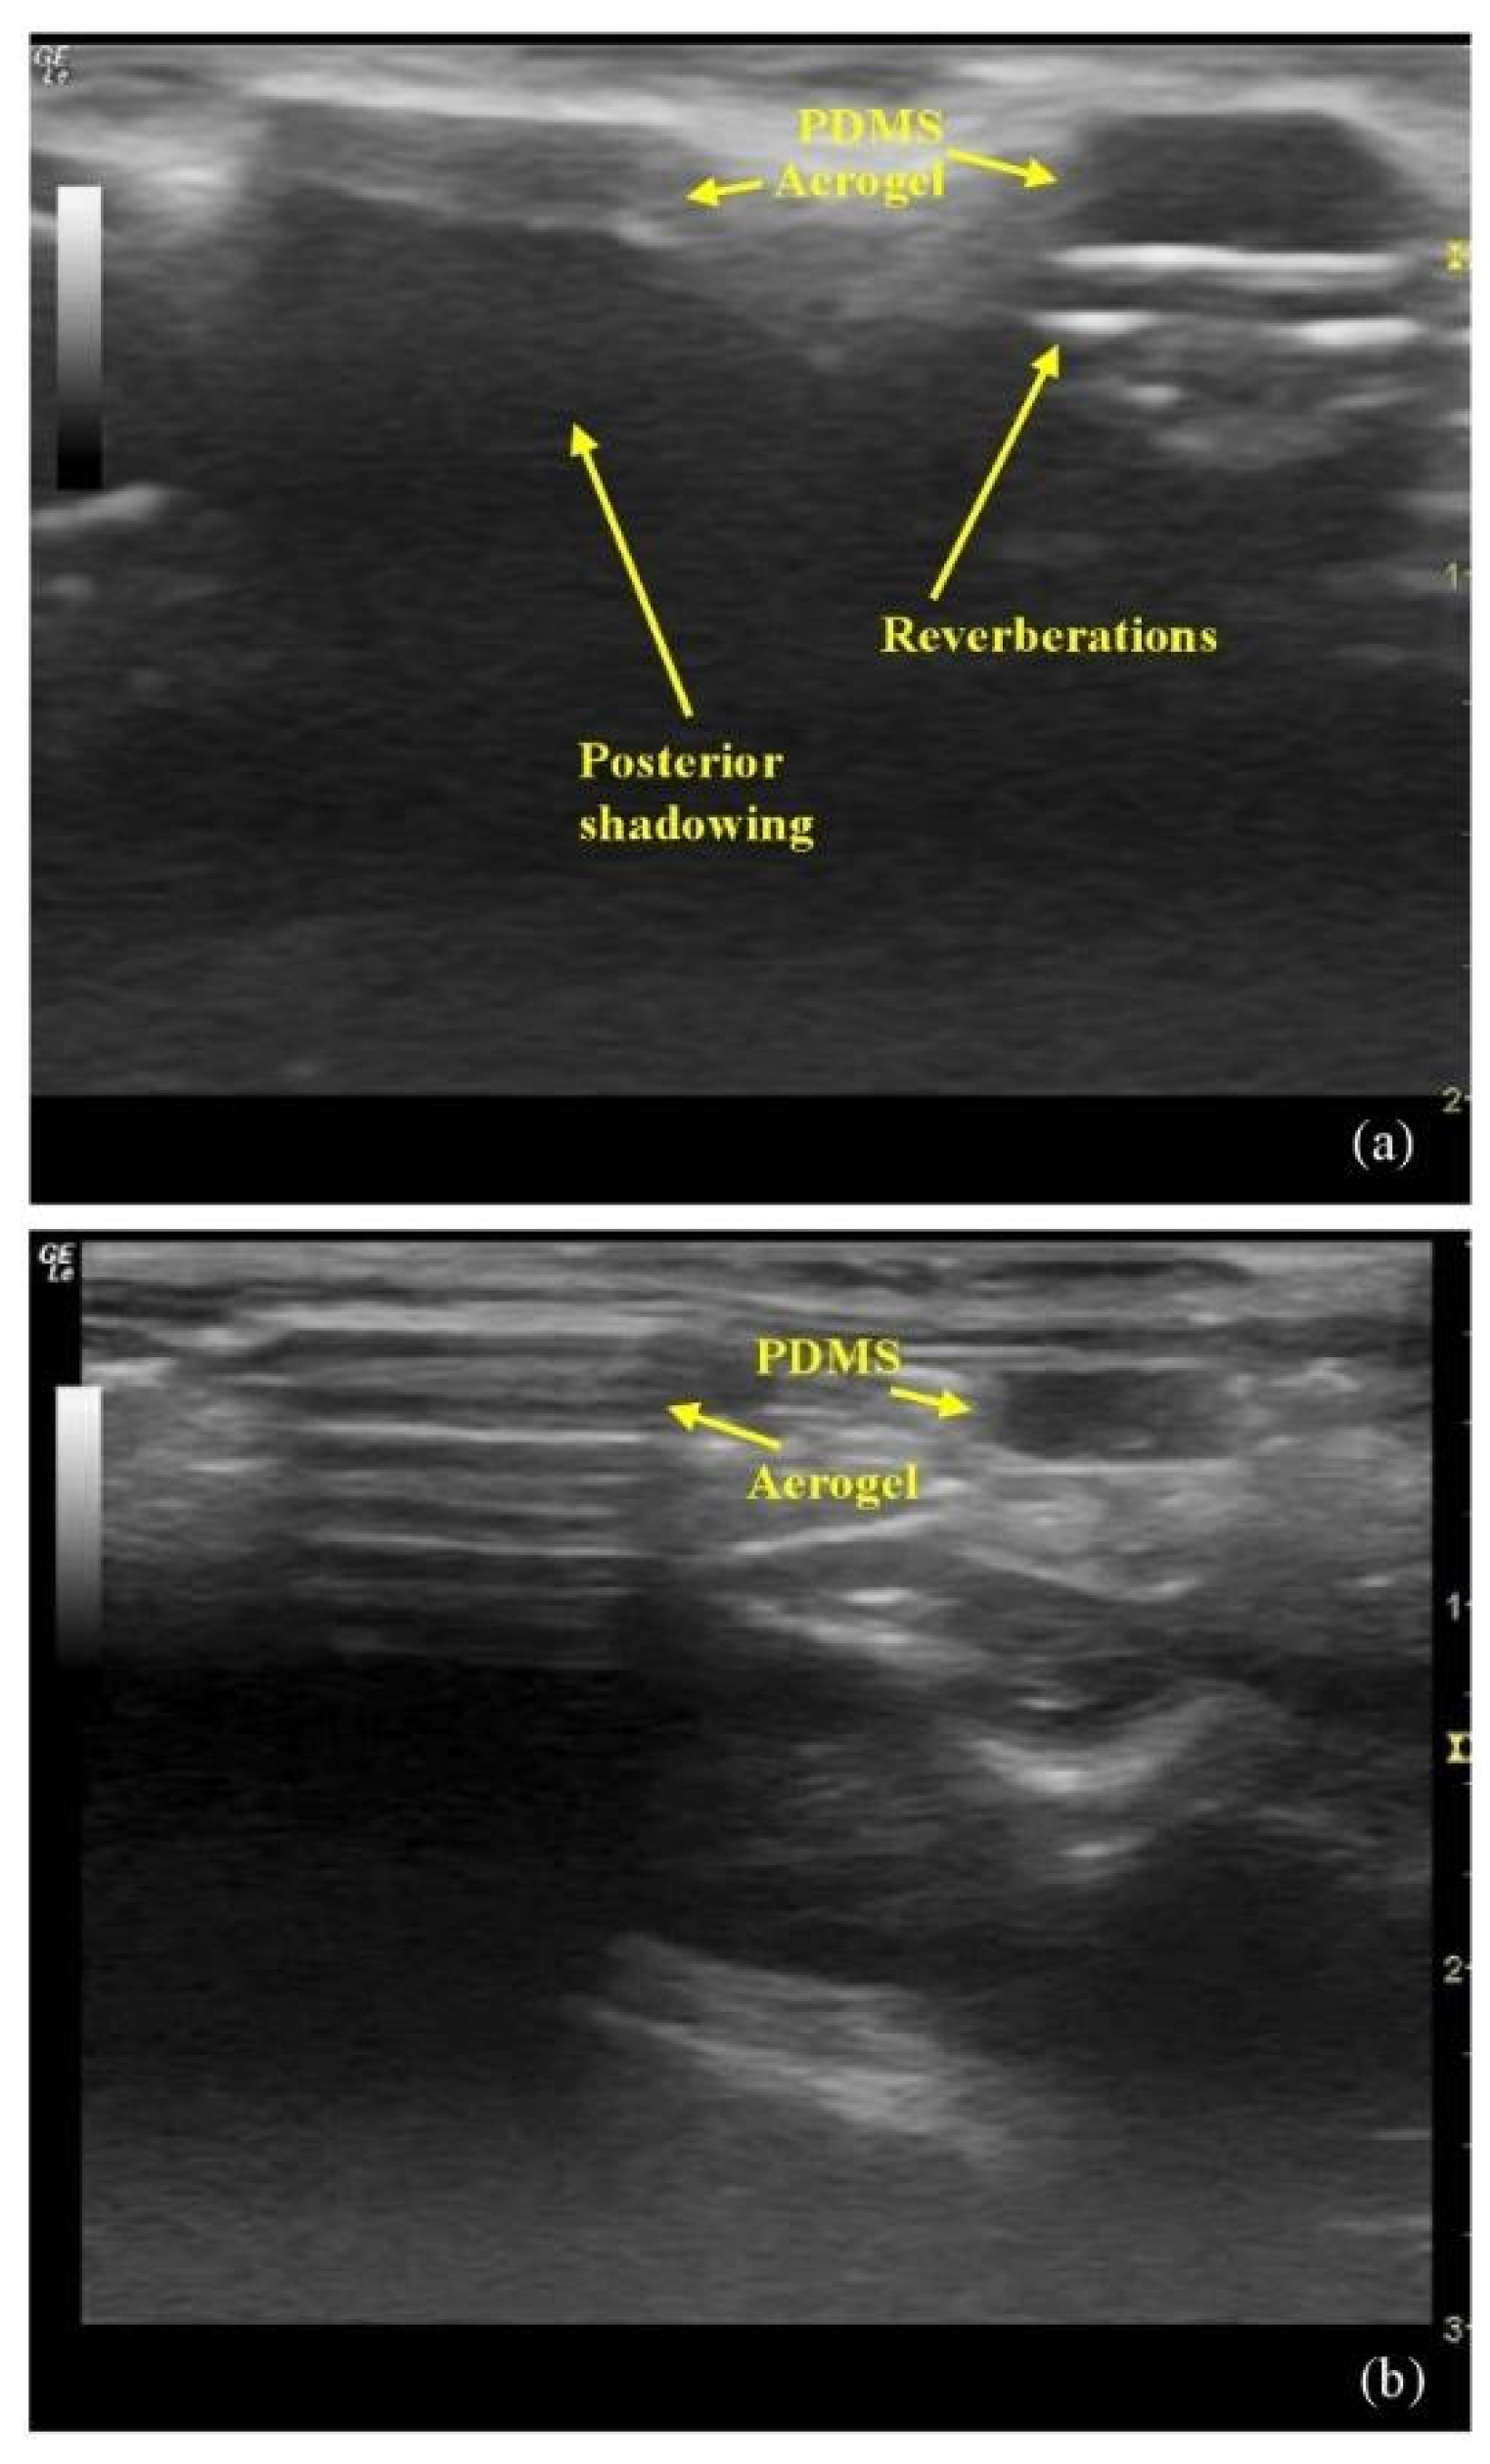

- Sabri, F.; Sebelik, M.E.; Meacham, R.; Boughter, J.D., Jr.; Challis, M.J.; Leventis, N. In vivo ultrasonic detection of polyurea crosslinked silica aerogel implants. PLoS ONE 2013, 8, e66348. [Google Scholar] [CrossRef]